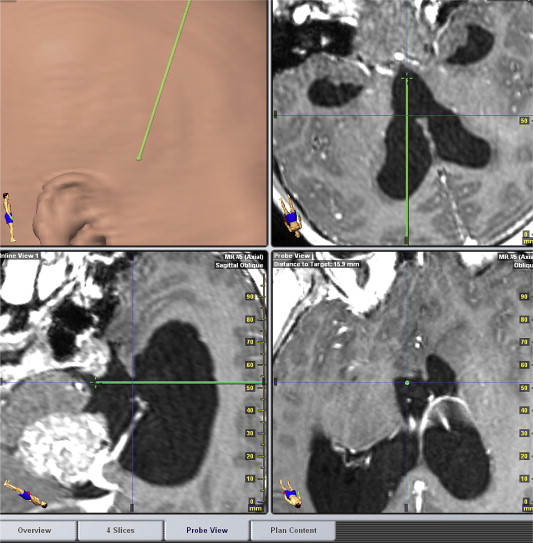

Measurement of the virtual displacement for endoscopic third ventriculostomy in ...

Figure 3.

Measurement of the virtual displacement for endoscopic third ventriculostomy in neuronavigation software (probe view): Case 3, displacement = 0 mm.